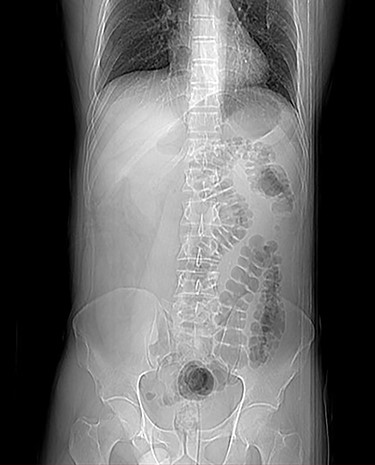

A 38-year-old male patient with neither known medical history nor former abdominal surgery was admitted to the emergency department with a 5-day history of abdominal pain associated with vomiting. He was hemodynamically stable and apyretic. The abdomen was moderately distended. Routine blood tests revealed only a mild electrolyte imbalance. Plain abdominal X-ray demonstrated a gastrectasia without significant bowel air-fluid levels (Fig. 1). A routine nasopharyngeal swab to detect SARS-CoV-2 infection with molecular real-time polymerase chain reaction test resulted positive. No respiratory symptoms or anomalies were discovered. The symptoms were referred to a gastroenteritis COVID-19 related and the patient was admitted to the Infectious Disease Hospital.